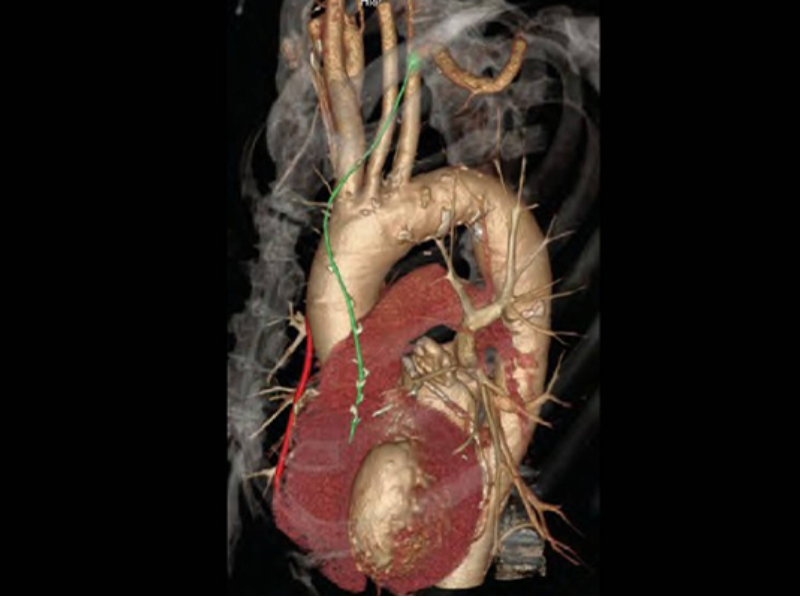

Coronary CTA

High Temporal Resolution CT